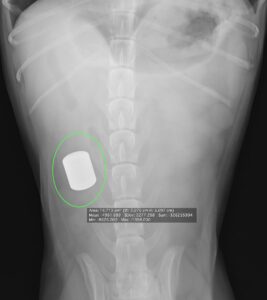

2023.05.22外科誤食しないでね 〜予想外なモノ飲み込みます〜 -